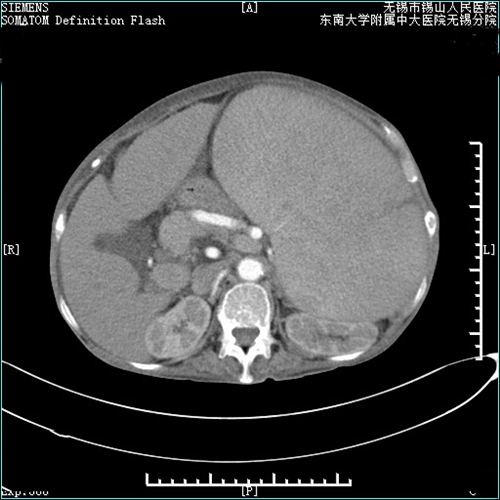

一月前,张阿姨皮肤黏膜多处瘀点瘀斑,牙龈出血,食纳下降,明显消瘦,并伴有口腔黏膜溃烂等症状。张阿姨在家人的陪同下来院就诊。血液肿瘤科主任张世强和副主任强金虎接诊后,将张阿姨收住入院,进一步检查后发现,张阿姨一度被外院诊断为“骨髓增生异常综合征(MDS)”,这一诊断引起了肿瘤血液科张世强主任和强金虎的注意。肿瘤血液科医疗团队组织了心内科、消化内科、肝胆外科、血管介入科、影像科等部门,开展MDT多学科会诊。结合患者的血液学、影像学等检查结果,普外科副主任兼肝胆外科副主任赵万文考虑患者为血吸虫肝病后的脾功能亢进,进行性导致脾大(Ⅲ度肿大),引起血液系统的明显改变(类白血病现象)。

随后,张阿姨转到了肝胆外科,开始完善术前准备。普外科医疗团队组织了科内疑难病重病理讨论。顾盐炎主任解析了血吸虫肝病的相关知识,针对患者病因、病情、诊断、影像资料、治疗策略等多方面进行分析指导,制定了周密的手术方案。